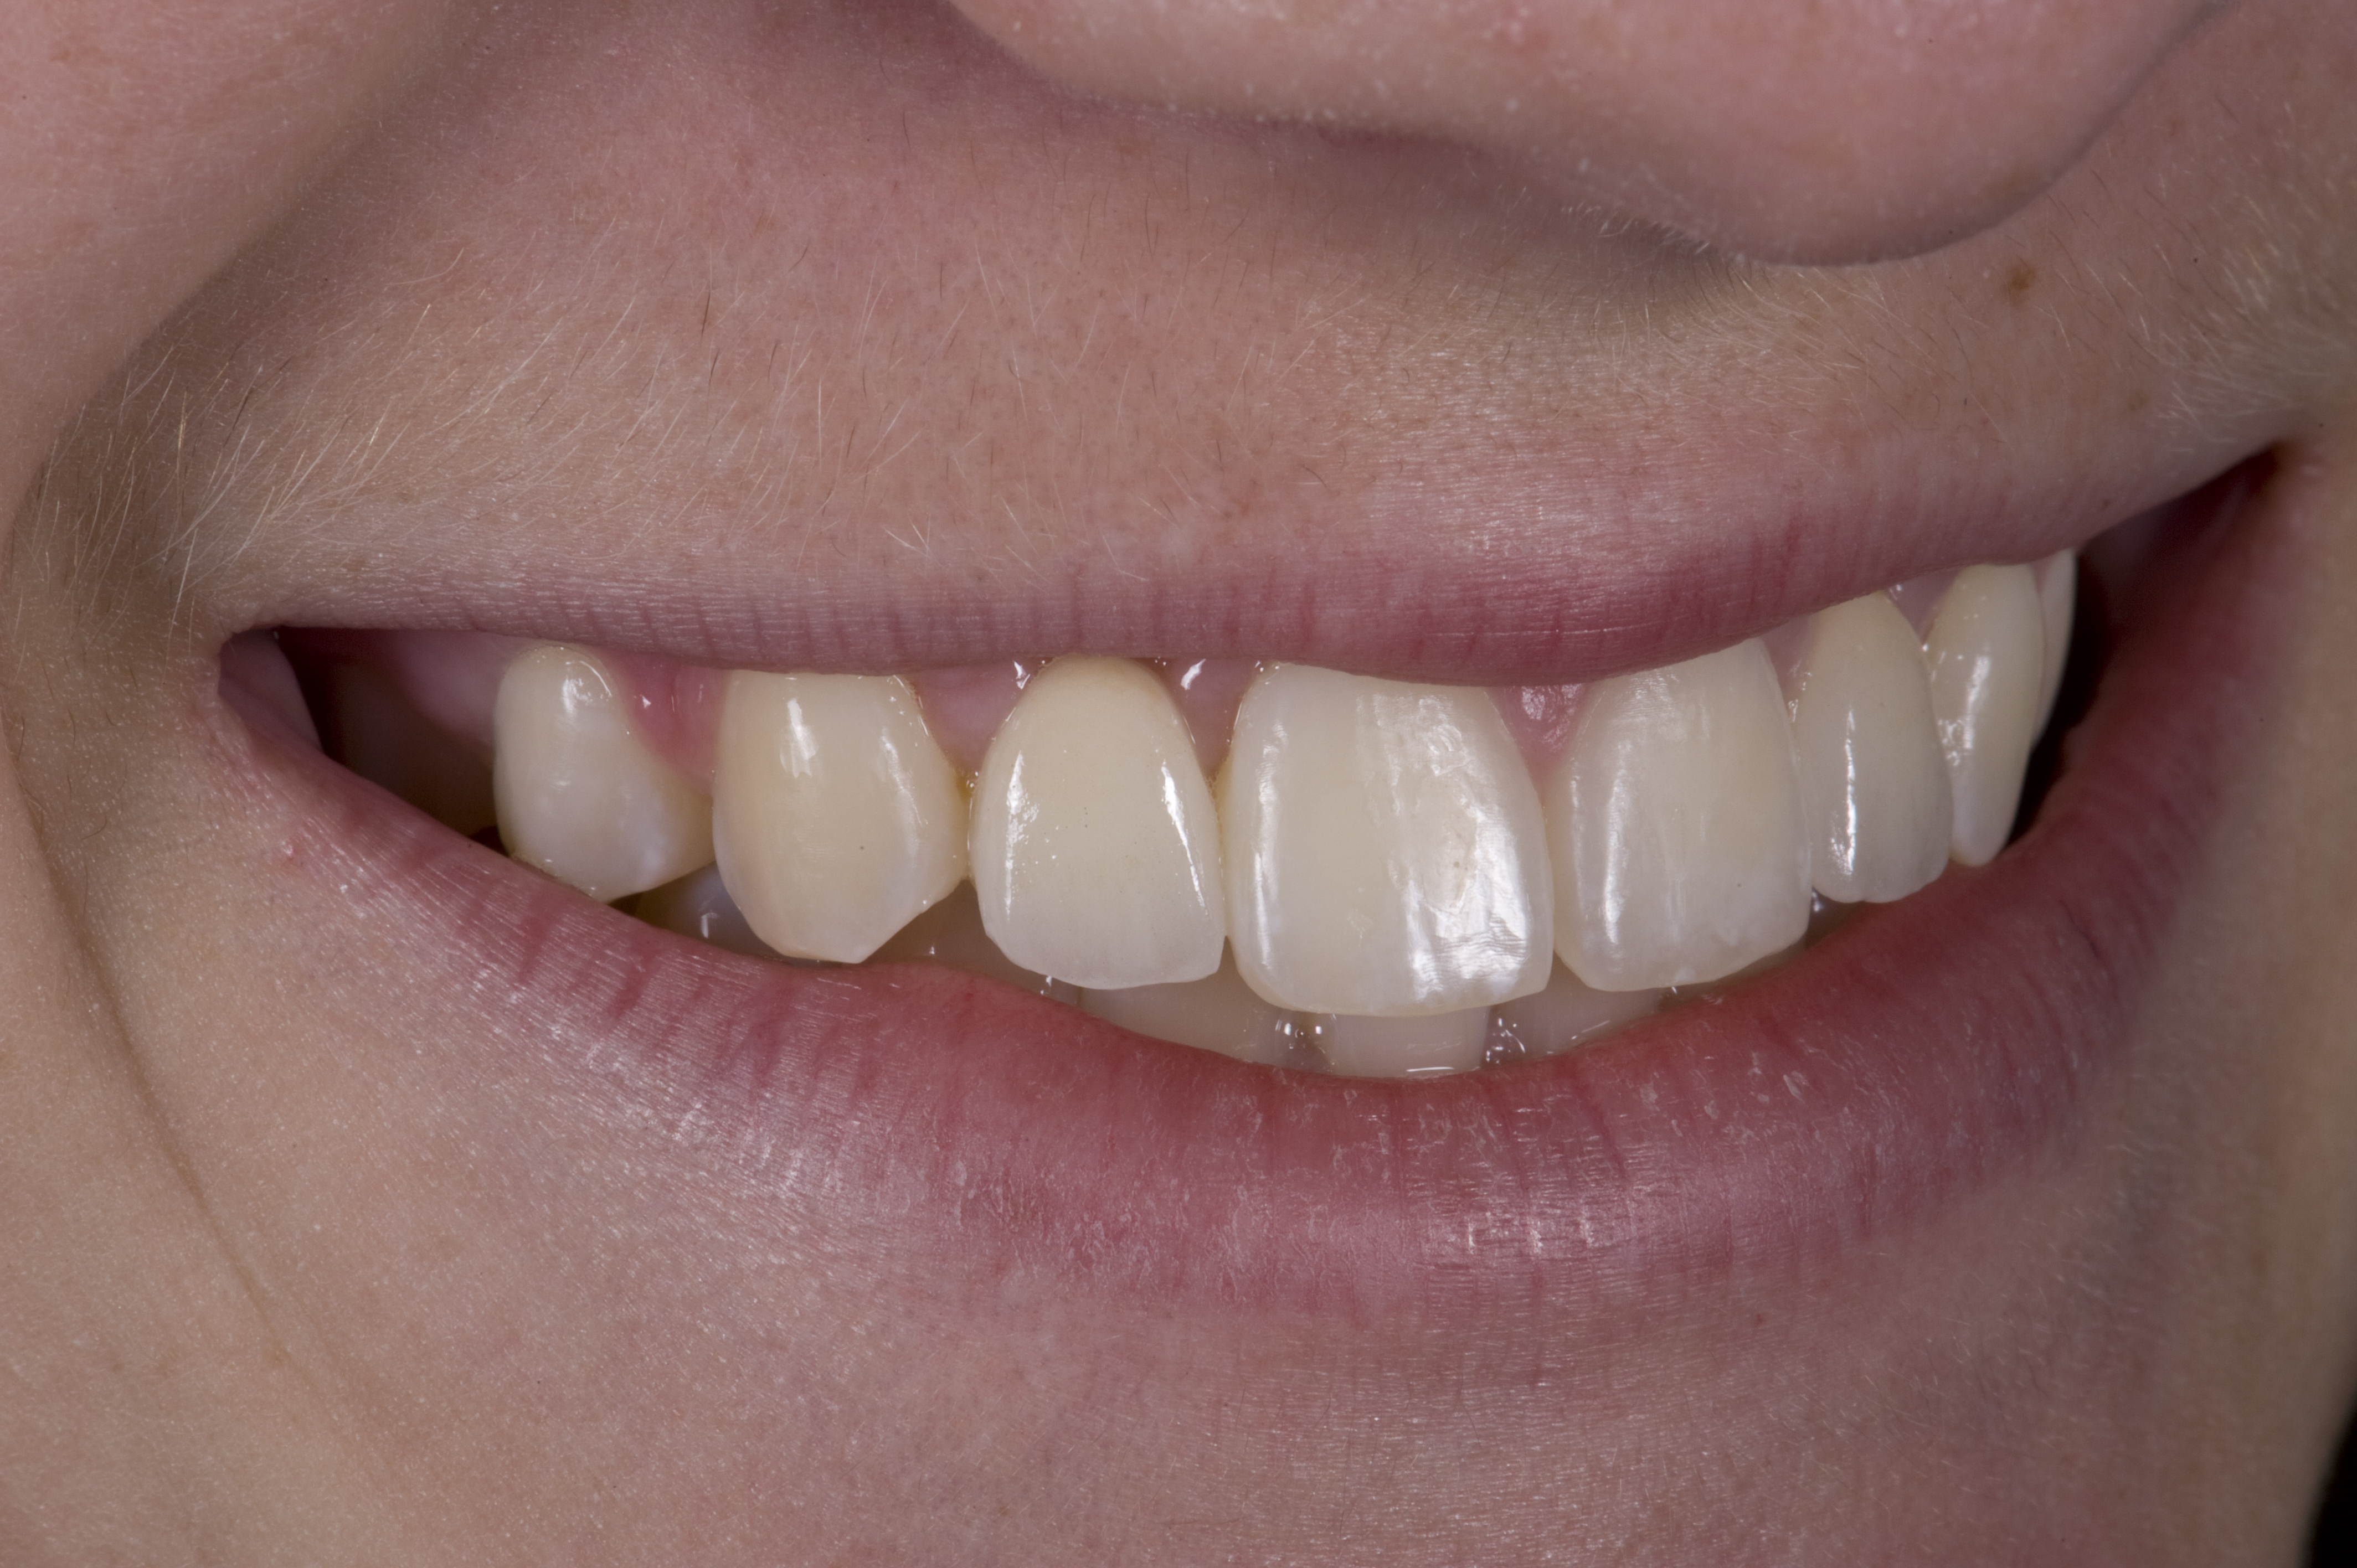

A 14-year-old patient presented to the office with his mother (Figure 1). His chief complaint involved the large spaces between the teeth created by his missing right maxillary lateral incisor and his small left maxillary lateral incisor. He desired to replace the missing tooth with an implant and create a beautiful smile. Upon examination, he was found to have a class I canine and molar relationship, but because he had a tooth size/arch size discrepancy and space distal to the right central incisor, the remaining incisors had drifted to the right. The left maxillary lateral incisor was peg-shaped and in a cross bite position. Studies have shown a clear association between congenitally missing teeth and reduced tooth size.59-62 Because he was only 14-years-old at the time and could not have implants placed until the cessation of growth (somewhere in the vicinity of 22 years old), he was sent to the orthodontist for alignment of the teeth.16,17 After 2 years of orthodontics, the appliances were removed, and his tooth coloration was improved using carbamide peroxide bleaching (Figure 2). Because some form of provisional needed to be placed until he was finished growing, a double-wing metal resin-bonded bridge was chosen. As discussed earlier, this is the ideal transitional prosthesis for patients that have congenitally missing maxillary lateral incisors. The benefits of this type of prosthesis include its ability to be removed and rebonded during the surgical phase of treatment and its ability to retain the roots in their proper position after orthodontic treatment.16 The final plan for the patient was to increase the width of the central and the maxillary left lateral incisor, utilizing porcelain laminate veneers to achieve the appropriate width/length ratio of 80%. A wax-up was created to idealize tooth size, a putty matrix was made from the wax-up to facilitate bonding of the incisors, and a non-precious, double-wing metal resin-bonded bridge was fabricated for lateral incisor replacement. Once the teeth were bonded to ideal size, the “Maryland Bridge” was fabricated from a polyvinyl arch impression with the newly bonded teeth (Figure 3). The metal frame was cast from a non-precious alloy to allow for fabrication of a very thin frame and to create a better surface for bonding. After sandblasting the internal aspect of the frame with CoJet™ silica (3M ESPE), accomplishing salinization, and executing cementation with a dual-cure resin cement, a fairly good adhesion to the frame was anticipated.29 The enamel surface was etched with phosphoric acid for 30 seconds, the primer (Single Bond Plus, 3M ESPE) was applied to both the internal surface of the sandblasted framework and the etched enamel, and the bridge was cemented with RelyX™ ARC (3M Espe) dual-cured resin cement (Figure 4 and Figure 5).

(1.) Initial presentation. Note midline shift to right, missing right lateral incisor, and diminutive left lateral incisor in crossbite.

Figure 1

(2.) After orthodontic alignment of teeth and bleaching. Note alveolar deficiency in right lateral incisor site and diminutive left lateral incisor.

Figure 2